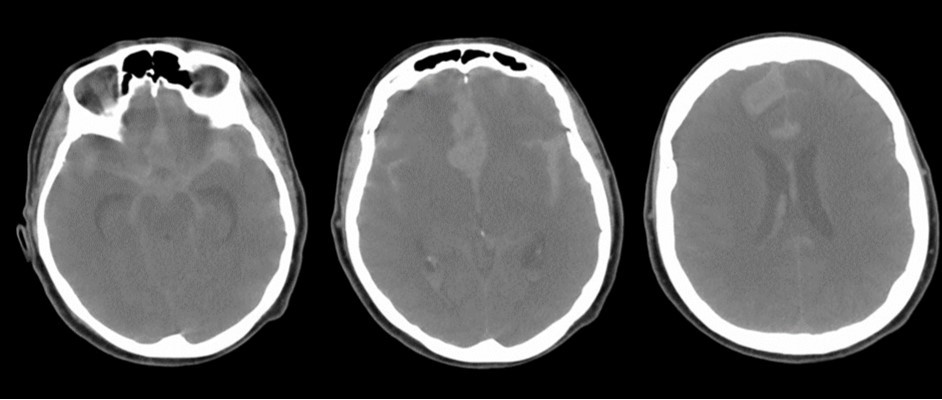

A 65 years-old woman with no relevant medical history was carried to the emergency department of another institution for the sudden onset of headache and vomiting, followed by loss of consciousness. She underwent a cerebral CT scan, that showed diffuse SAH in the basal cisterns and anterior interemispheric fissure (Figure 1). The CT angiogram displayed a single aneurysm of the anterior communicating artery, that local radiologists considered unfavorable for endovascular treatment. The patient was therefore surgically managed, with left pterional craniotomy for aneurysm clipping and right external ventricular drain (EVD) positioning. In the following days the woman reacquired alertness; the EVD was removed without need of permanent shunting and she was transferred to rehabilitation four weeks after the operation in quite good conditions.

Figure 1.Non-contrast axial CT scan showing thick subarachnoid hemorrhage in the basal cisterns and in the frontal interemispheric space

The clinical and radiological features of these two diseases are perfectly known to neurosurgeons; anyhow our case shows that trouble rises when they do occur simultaneously. The patient we described had initially acute signs due to SAH and later signs that were incorrectly interpreted as SAH-related. The tumor was almost invisible -because of its likely small volume and thick SAH- in the first CT performed (Figure 1). Analyzing the early follow-up CT (Figure 2) anyway things do not seem so clear. In the frontal region remained too much fogging close to the midline; the asymmetric distribution of such alteration should had point out a problem, but everybody kept thinking to a “simple” post-hemorrhagic condition, due to ventricular enlargement and focal ischemia. The initial mental impairment of that period was equally attributed to a normal SAH result with moderate hydrocephalus. The proper diagnosis of glioma happened late, and the patient was at that point unable to have significant benefits from surgery.